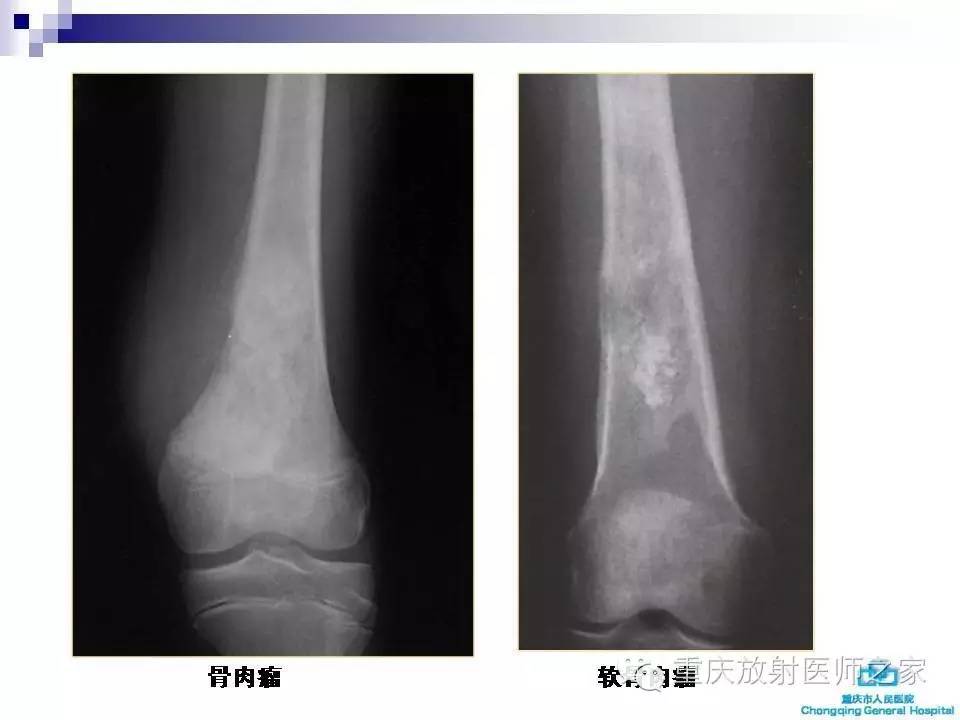

骨肉瘤的影像学诊断及鉴别诊断

软骨肉瘤的影像学表现